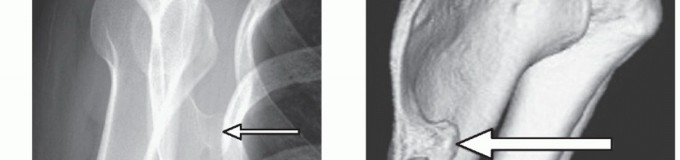

Computed Tomography (CT) with 3D volumetric reconstruction is the gold standard for evaluating the osseous morphology of the superomedial angle. It precisely delineates the anterior curvature of the scapula, identifies osteochondromas, and assesses thoracic cage congruency.

Magnetic Resonance Imaging (MRI), particularly T2-weighted and STIR sequences, is indispensable for evaluating soft tissue pathology. MRI effectively demonstrates bursal fluid, synovial hypertrophy, fibrotic masses, and soft tissue tumors (e.g., elastofibroma dorsi) that may be responsible for the mechanical snapping.

Epidemiologically, snapping scapula syndrome is most prevalent in young, active patients, particularly those involved in sports requiring repetitive overhead motion, such as baseball, swimming, and gymnastics. The etiology is generally multifactorial, encompassing osseous abnormalities, soft tissue variations, and dynamic neuromuscular imbalances leading to scapular dyskinesis. While primary osseous lesions like osteochondromas or rib exostoses are classic causes, the vast majority of cases are secondary to chronic microtrauma, resulting in fibrotic changes within the periscapular bursae and subsequent impingement of the superomedial angle of the scapula against the posterior thoracic wall.